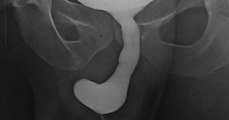

Check out our official website: http://us.tomonews.net/<br />Check out our Android app: http://goo.gl/PtT6VD<br />Check out our iOS app: http://bit.ly/1gO3z1f<br /><br />-------------------------------------------------------------<br /><br />Men slipping and landing with their penises stuck in something is a health hazard world governments have ignored for too long! <br /> <br />It happened just the other day after a Chinese painter in Fujian Province was painting in a hot room.<br /> <br />As temperatures soared, he had an idea: paint in the nude! -Something we're sure many an artist has tried before.<br /> <br />61-year-old Lian Tian explained that as he was walking around his apartment, he suddenly slipped, and found himself and his selfhood stuck in a pipe that connects to an air con.<br /> <br />Feeling embarrassed and sure no one would believe him, Lian hung out for 2 days until infection started setting in. Finally, he called for help and it took rescuers four hours and an electric saw to free the artist's masterpiece. Lian says he knows no one would believe his tale. But we at TomoNews aren't cynics...tell us in the comments how and why you totally believe his explanation.<br /><br />-------------------------------------------------------------<br /><br />Welcome to TomoNews, where we animate the most entertaining news on the internets. Come here for an animated look at viral headlines, US news, celebrity gossip, salacious scandals, dumb criminals and much more! Subscribe now for daily news animations that will knock your socks off.<br /><br />Check out our Android app: https://play.google.com/store/apps/details?id=com.nextmedia.gan<br />Check out our iOS app: https://itunes.apple.com/app/tomonews/id633875353<br /><br />For news that's fun and never boring, visit our channel:<br />https://www.youtube.com/user/TomoNewsUS<br /><br />Subscribe to stay updated on all the top stories:<br />https://www.youtube.com/channel/UCt-WqkTyKK1_70U4bb4k4lQ?sub_confirmation=1<br /><br />Stay connected with us here:<br />Facebook http://www.facebook.com/TomoNewsUS<br />Twitter @tomonewsus http://www.twitter.com/TomoNewsUS